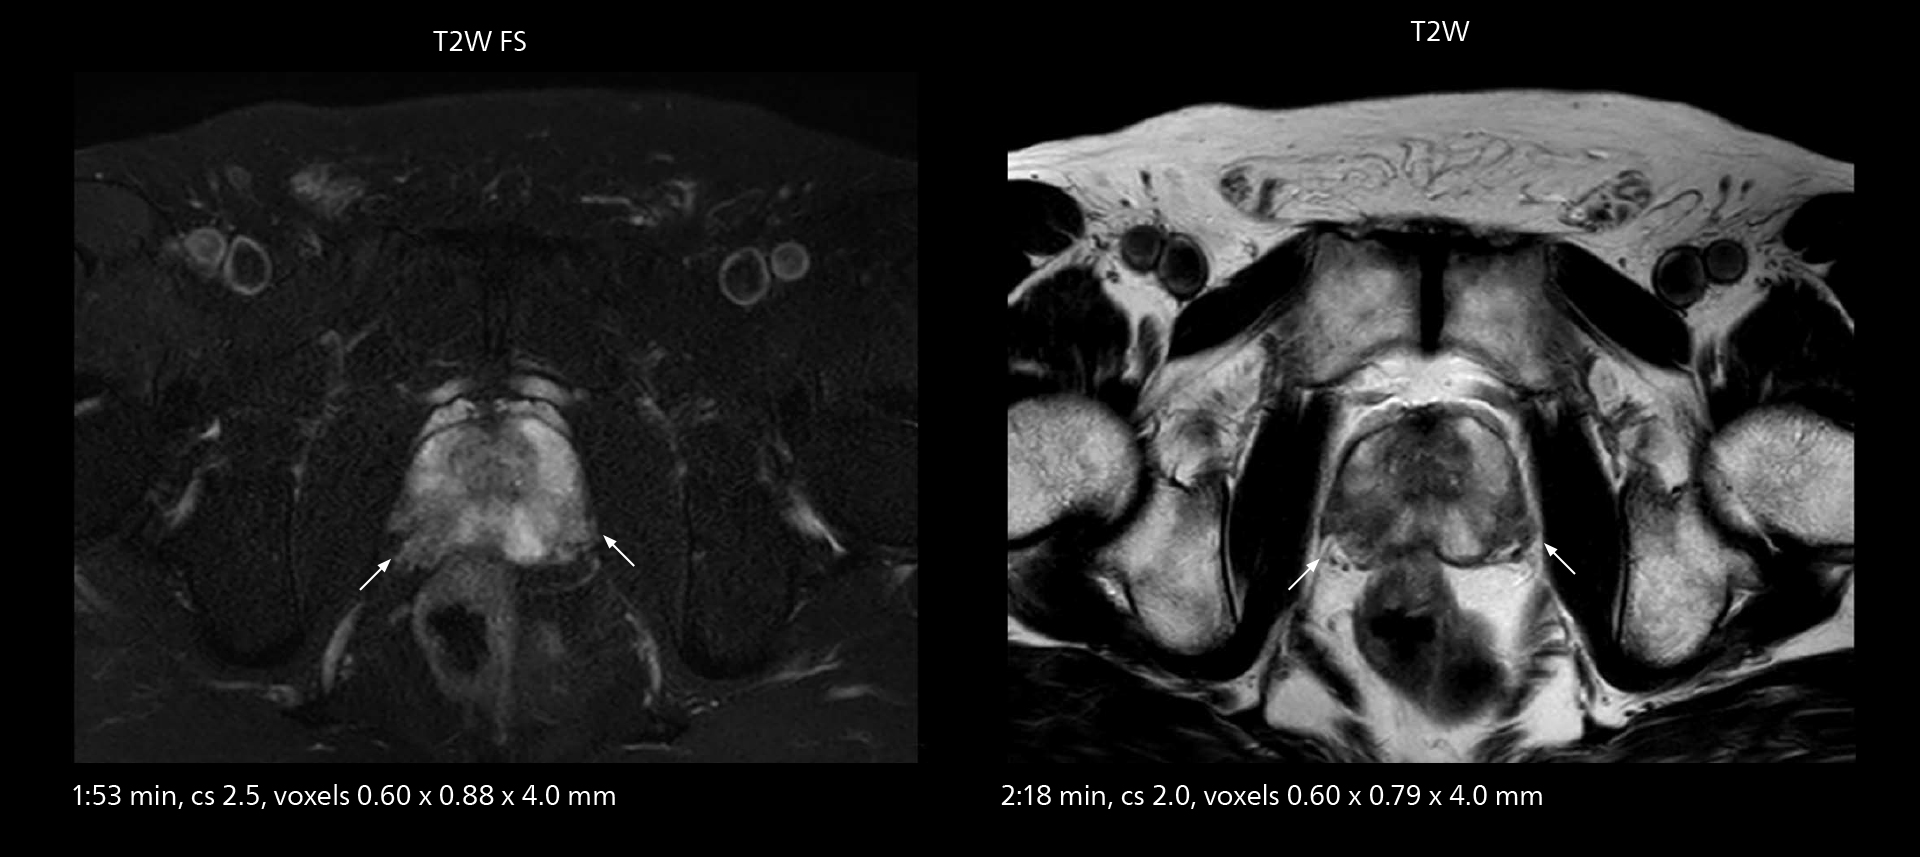

Examples of prostate imaging showing faster scan times and improved resolution illustrate the power of SmartPath to Elition X in this case of prostate cancer with PI-RADS score 4.